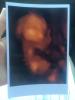

@musel, у вас такие кадры хорошие, и лицо, и ручки и тело👍👶

Фото в 20 недель в Ультрамеде дали это что-то😂😂😂Муж спросил - а где тут лицо? А я сама не знаю😱🙈в 24 недели фото было уже суперским!👍Правда в Семье, и мне кажется у них аппарат лучше все же🤗☝️

Были в ультрамед на Достоевского, все понравилось, только маленькая она ещё, фото пока не очень, да и оно там вроде как бонусом идёт вместе с видео. С сыном в первую беременность фото в 32 недели делали, очень даже похож был)